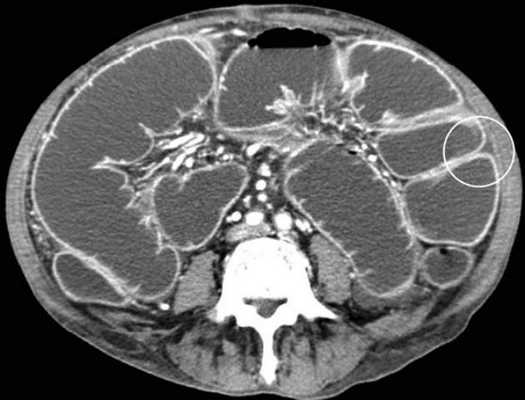

Мальротация кишечника (нонротация) у мужчины 39 лет.

(а, б) Тощая кишка — прямое продолжение двенадцатиперстной (стрелка, а), отсутствуют нормальные 3-й и 4-й сегменты двенадцатиперстной кишки, а также двенадцатиперстно-тощекишечный переход (звездочка, б).

(в, г) Петли тонкой кишки (прямые стрелки) лежат в левой половине брюшной полости, а ободочная кишка (изогнутые стрелки) — в правой половине. Заворот средней кишки у мальчика 11 лет.

(а) При КТ с контрастированием в аксиальной проекции выявлена транспозиция верхней брыжеечной артерии (указатель) и вены (стрелка).

(б, в) На более низких уровнях при КТ в аксиальной проекции выявлен симптом «водоворота» (стрелка), представляющий собой перекручивание верхней брыжеечной вены и ее ветвей, брыжеечного жира и петель кишки вокруг верхней брыжеечной артерии по часовой стрелке.

Врожденная мальротация кишечника обусловлена нарушением нормальной ротации первичной кишки в направлении против часовой стрелки. Среди широкого разнообразия вариантов мальротации в клинической практике наиболее часто встречают полное отсутствие ротации (нонротация). При этом состоянии тощая кишка служит прямым продолжением двенадцатиперстной, при этом отсутствуют 3-й и 4-й сегменты двенадцатиперстной кишки и двенадцатиперстно-тощекишечный переход. Петли тонкой кишки лежат в левой половине брюшной полости, а ободочная кишка — в правой половине. При завороте средней кишки ножка брыжейки сужена, а двенадцатиперстно-тощекишечный переход (местонахождение связки Трейтца) чаще расположен низко, по правую сторону от средней линии. Такие условия приводят к перекручиванию неправильно фиксированной тонкой кишки, а верхние брыжеечные артерия и вена располагаются в короткой и суженной ножке брыжейки.